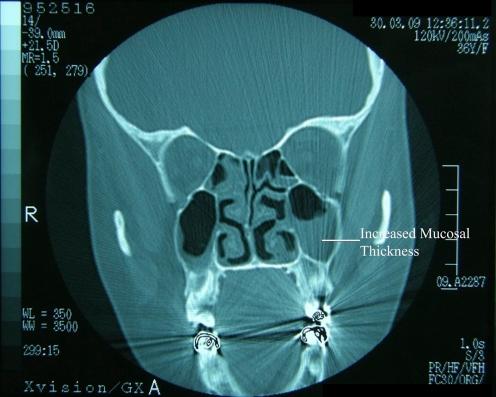

Acute maxillary sinusitis detected by bedside emergency department ultrasonography.